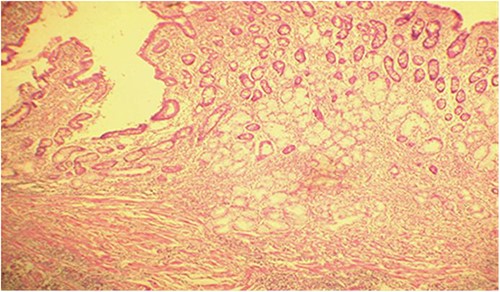

Microscopic analysis of various samples showed a transparietal massive infiltration of eosinophils with over 25% epithelial exocytosis and no granulomatous lesions or parasitic agents (Figs 3 and 4). Lymph nodes sampled from the congestive mesentery were reactive. The diagnosis of eosinophilic enteritis was established. The postoperative course was rapidly favorable, with weight gain. The patient was readmitted, and etiological assessment as well as a search for other locations, including hepatic and osteomedullary biopsies, returned negative results.

Diffuse infiltration of eosinophilic polymorphonuclear leukocytes affecting all layers of the jejunal wall (hematoxylin–eosin staining, magnification × 100).